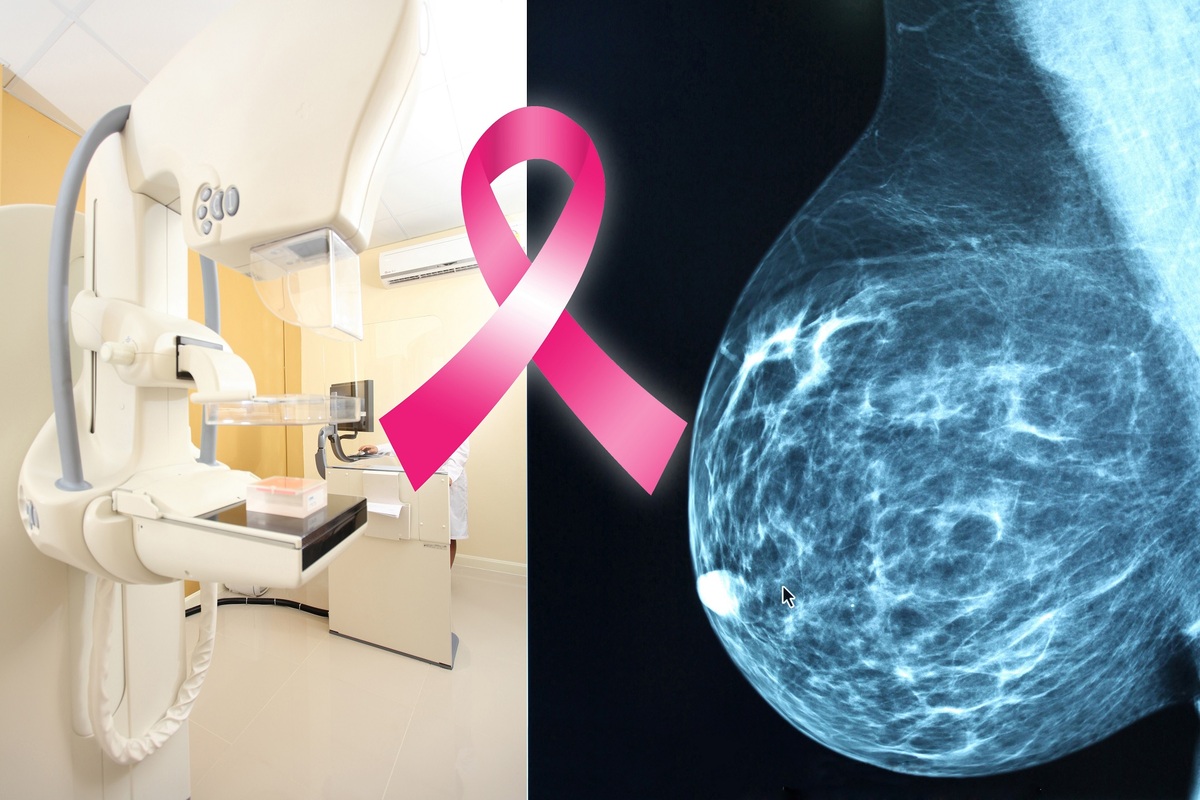

mammogram machine and mammogram image of breast with breast cancer ribbon in middle of collage

A mammogram is a radiographic image that gives a picture of the internal structure of the breast. There are two types of mammography: screening and diagnostic.

A screening mammogram is performed on women who have no evidence of breast disease. Using a mammography machine, a radiologic technologist obtains two views of each breast. Screening mammography is the best way to detect breast cancer early. A screening mammogram is similar to other screening exams such as a PAP smear, PSA for prostate cancer, fecal occult blood to detect colon cancer and a glucose test to detect diabetes.

Yearly screening mammography should be a routine procedure for all women ages 40 and older. Women with a strong family history (mother, sister or daughter) of premenopausal breast cancer may wish to begin screening earlier.

Diagnostic mammography is performed when a possible abnormality, such as a lump, has been found on a screening mammogram or upon clinical examination of the breast. It includes special views in order to better evaluate the abnormality. A diagnostic mammogram is read by the radiologist at the time of the exam.